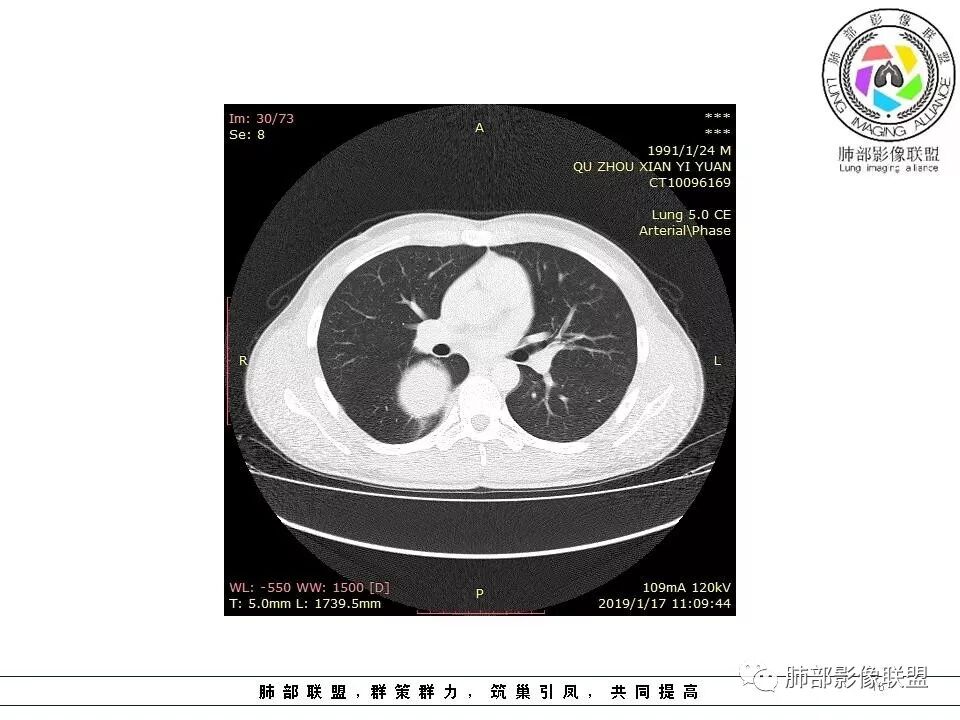

青年男性,间断胸痛;右侧脊柱旁可见一类圆形软组织密度影,密度欠均匀,增强扫描呈轻中度持续强化,邻近肺组织及肺动脉推移,可见肋间动脉供血,部分胸膜下脂肪可见,部分层面似见与右侧椎间孔相连。考虑后纵隔神经源性肿瘤。

青年男性,右侧脊柱旁软组织肿块,边缘膨隆,密度不均,临近肺组织受压、胸膜增厚,增强后动脉期呈不均匀强化,并可见肋间动脉供血,延迟期强化较均匀,定位肺外,首先考虑SFT,神经源性肿瘤待排

青年男性,右侧后纵膈肿块,有胸膜尾征,支气管被推压,定位肺外,脏胸膜?血供来自肺动脉及肋间动脉,增强后有强化,蛇纹征,考虑SFT,鉴别鞘瘤

3.相邻椎间孔未见扩大,也未见块影延入椎管,易起自于神经根的鞘瘤似乎找不到支持点。

可惜未提供矢状位骨窗图像,如在肋骨内下缘观察到压迹有助于肋间神经的鞘瘤的判断,这是因为二者之间密切的毗邻关系。

4.静脉期轻度不均匀强化,注意不是环形强化,亦未见明确的“AB区”,这点也不支持神经鞘瘤。临床及病灶轻度强化都不支持副节瘤。

尽管神经纤维瘤的诊断确实有些出乎意外,但病例开阔了我们的视野。